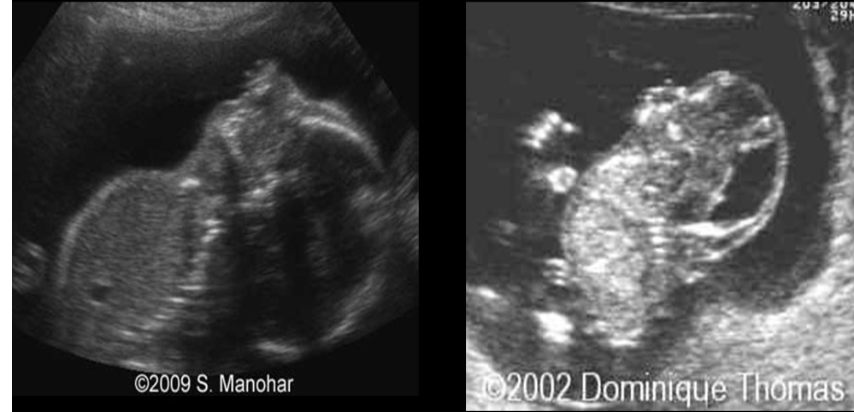

a) osteogenesis imperfecta

b) arthrogryposis

c) thanatophoric dysplasia

d) ellis van creveld syndrome